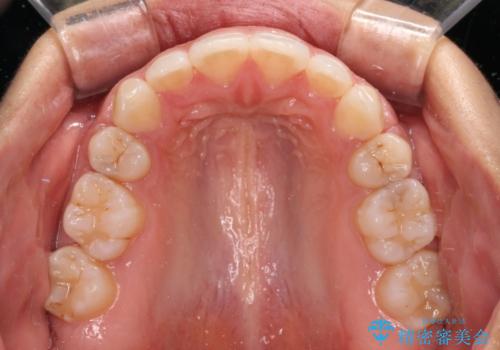

2年から2年半の治療期間を想定しており、予定通りの期間で無事に終了することができました。

唇や顎先に力を入れないなくてもスムーズに唇を閉じることができるようになりました。